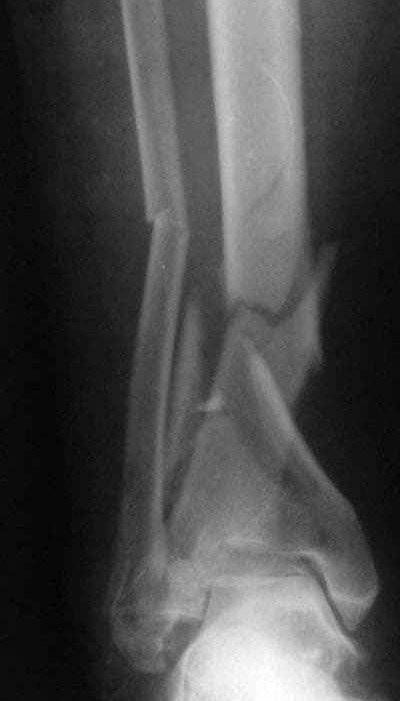

У мужчины перелом и сдвиг шейного отдела позвоночника, перелом голени и руки. Мужчину прооперировали но до сих пор не приходит в себя. Авторы: СОФЬЯ КАЛИНИЧЕНКО и ОЛЕГ ЧЕРДАНЦЕВ